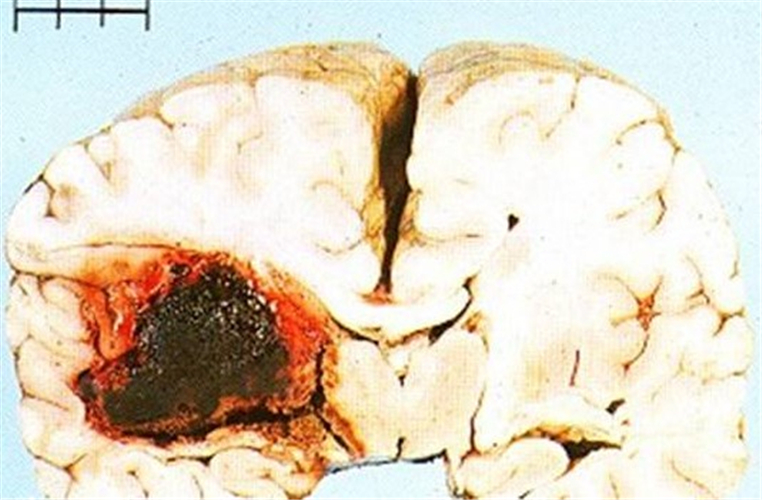

左大腦中動脈栓塞腦梗塞

液化性腦梗塞